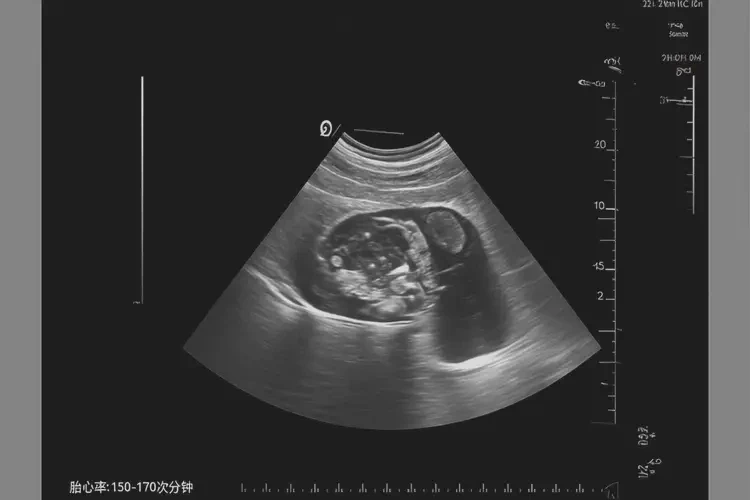

胎心率72次/分钟在怀孕2个月时可能存在风险。正常情况下,怀孕2个月的胎心率应在150-170次/分钟之间。胎心率低于120次/分钟可能表示胎儿心动过缓,需要进一步监测和评估。

胎心率是指胎儿心脏每分钟跳动的次数,是评估胎儿健康状况的重要指标之一。正常胎心率范围

- 怀孕早期(1-3个月):胎心率通常在150-170次/分钟之间。